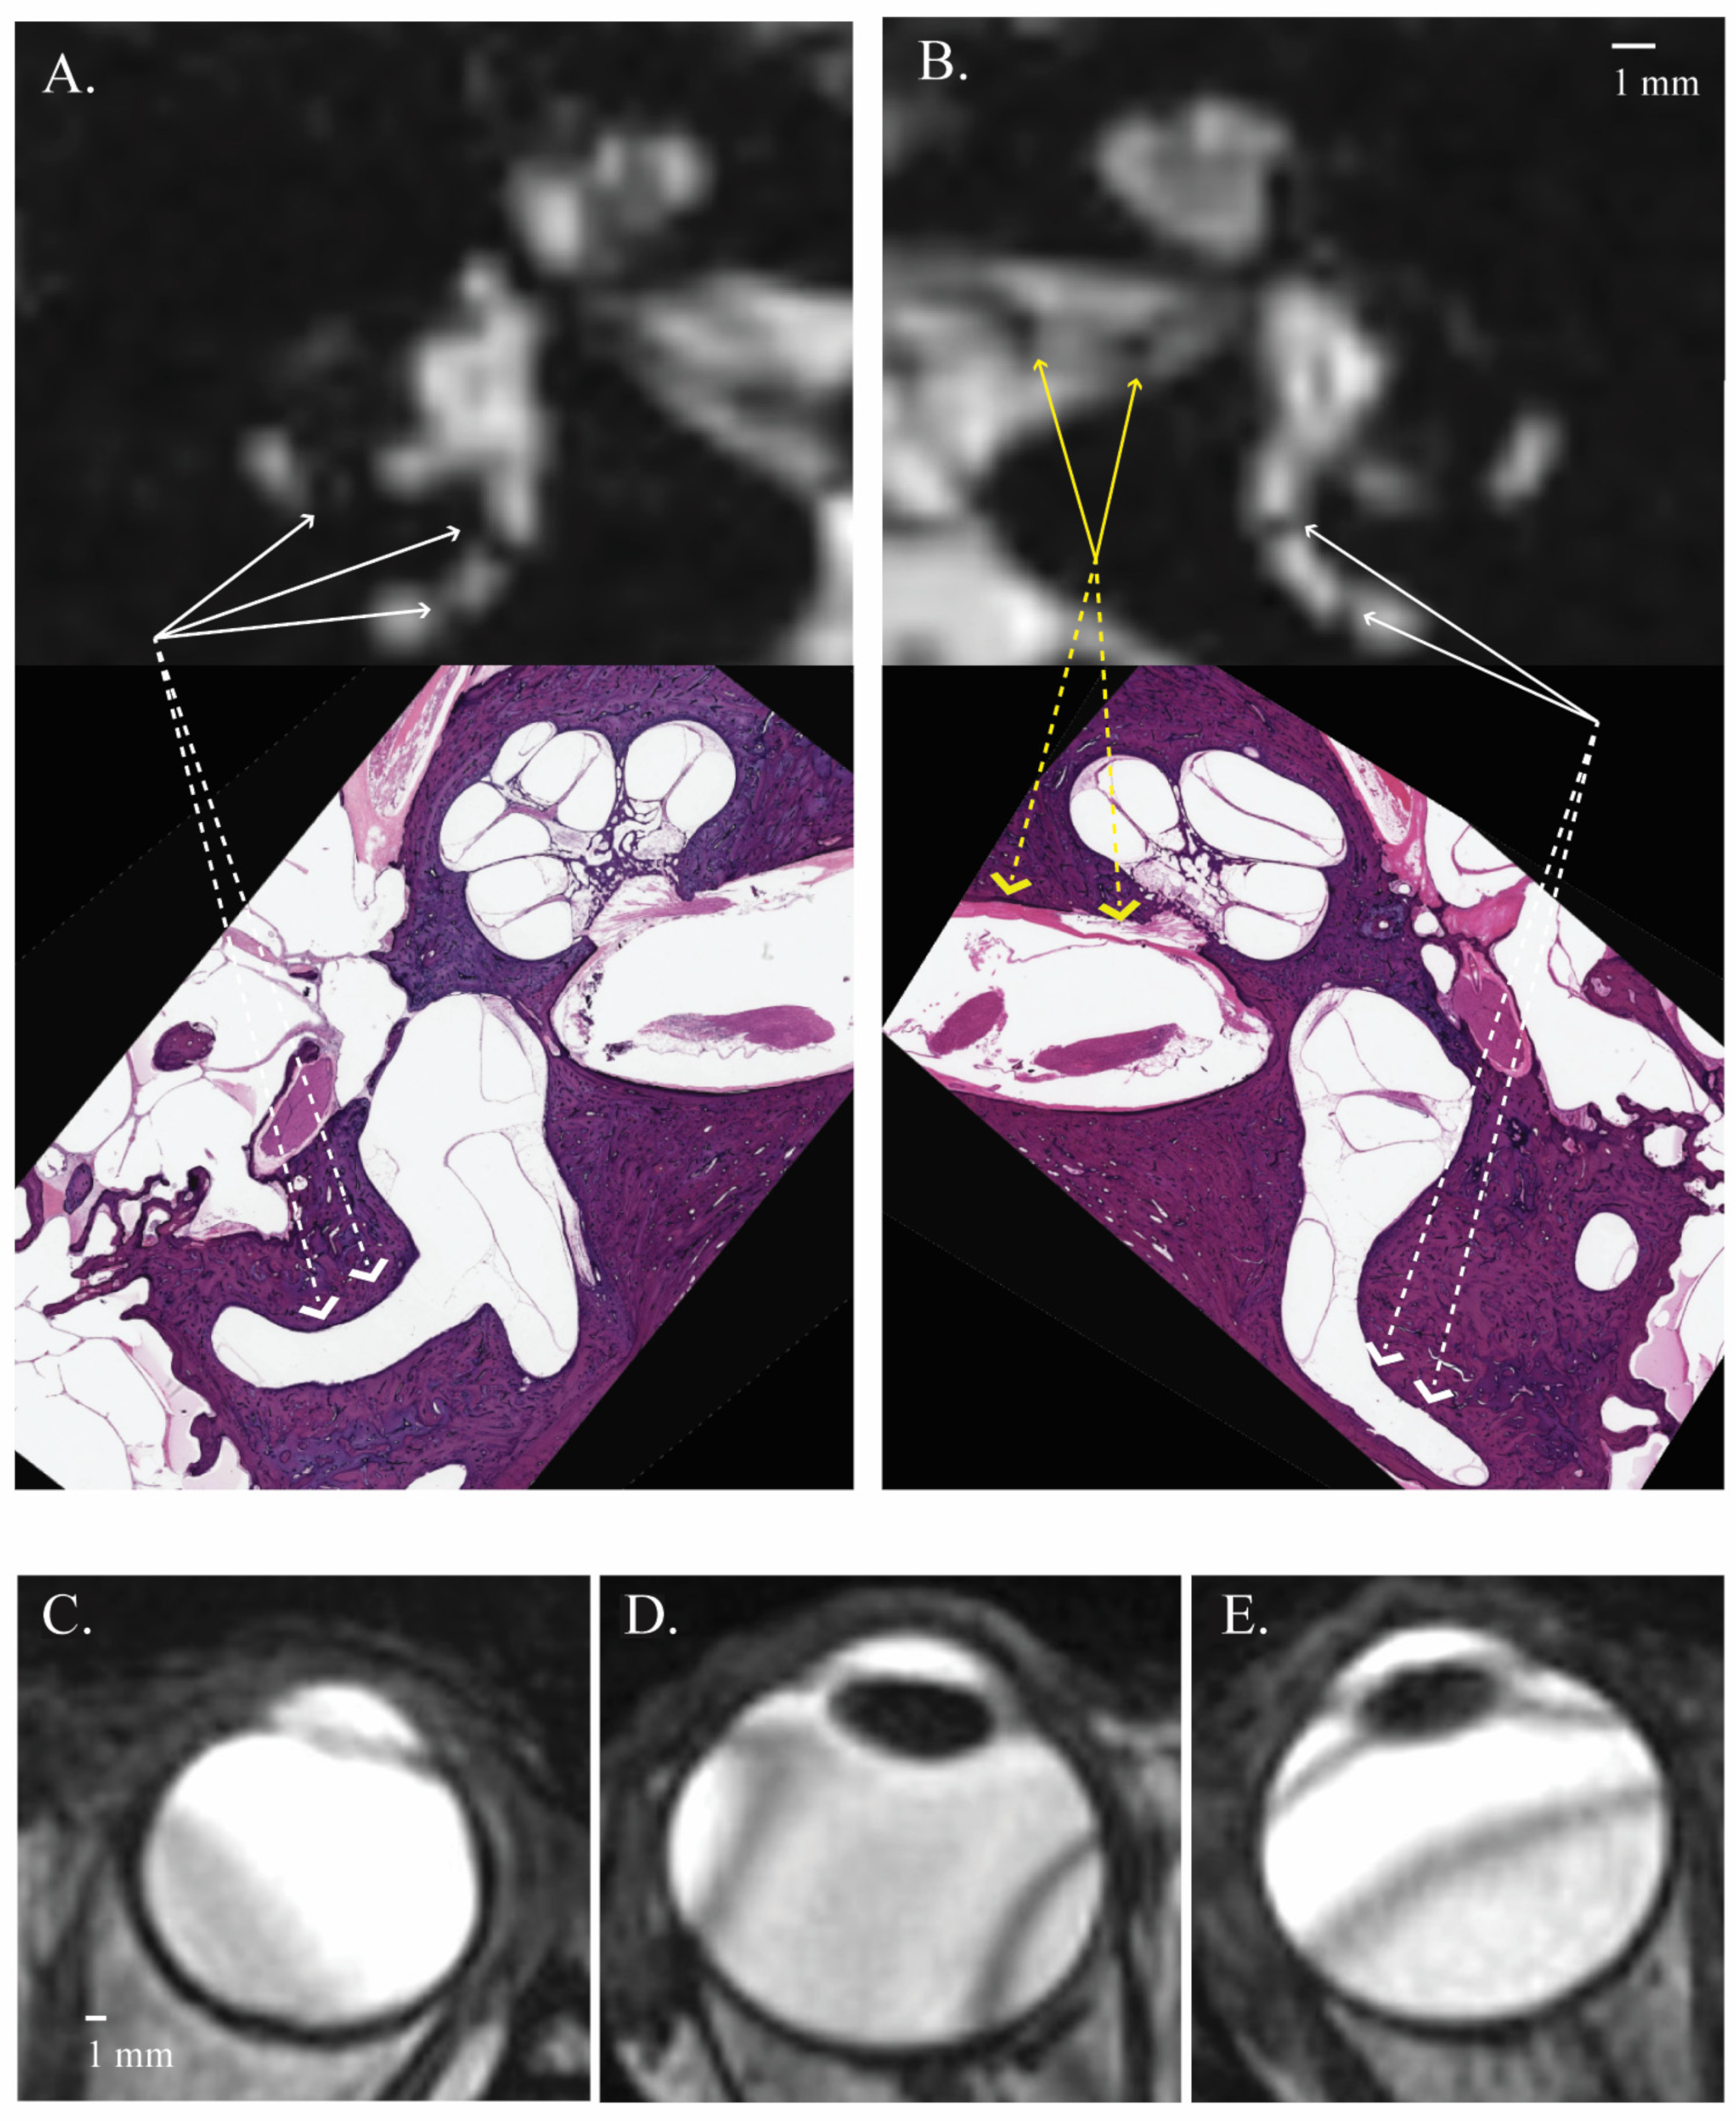

3.1. Signal Areas in the Inner Ear

3.2. Signal Areas in the Eye

| Regions of Low Signal Intensity within the Inner Ear (n) | ||||||||||

|---|---|---|---|---|---|---|---|---|---|---|

| A | B | C | D | E | F | G | H | I | ||

| Right ear | Reader 1 | 8 | 6 | 6 | 7 | 9 | 9 | 8 | 10 | 10 |

| Reader 2 | 8 | 6 | 5 | 7 | 9 | 9 | 8 | 9 | 10 | |

| Left ear | Reader 1 | 10 | 7 | 4 | 7 | 10 | 10 | 8 | 10 | 10 |

| Reader 2 | 10 | 7 | 4 | 7 | 10 | 10 | 8 | 10 | 10 | |

| Regions of Low Signal Intensity (n) | |||||||||

|---|---|---|---|---|---|---|---|---|---|

| A | B | C | D | E | F | G | H | I | |

| Right ear | 27 (90.0%) | 21 (70.0%) | 10 (30.3%) | 22 (73.3%) | 28 (93.3%) | 29 (96.7%) | 24 (80.0%) | 29 (96.7%) | 30 (100%) |

| Left ear | 28 (93.3%) | 21 (70.0%) | 14 (46.7%) | 25 (83.3%) | 26 (86.7%) | 29 (96.7%) | 26 (86.7%) | 30 (100%) | 30 (100%) |

| Banding Artifacts of the Eye | |||

|---|---|---|---|

| Mean (SD) Number of Bands in the Eye (n) | Mean (SD) Internal Angle of the Banding Artifacts (°) | Mean (SD) Angle of Banding Artifacts in Relation to the Optic Nerve Plane (°) | |

| Right eye | * 1.47 (1.41) | * 142.60 (13.76) | 58.01 (24.66) |

| Left eye | * 1.27 (0.64) | * 148.10 (14.21) | 54.47 (24.46) |